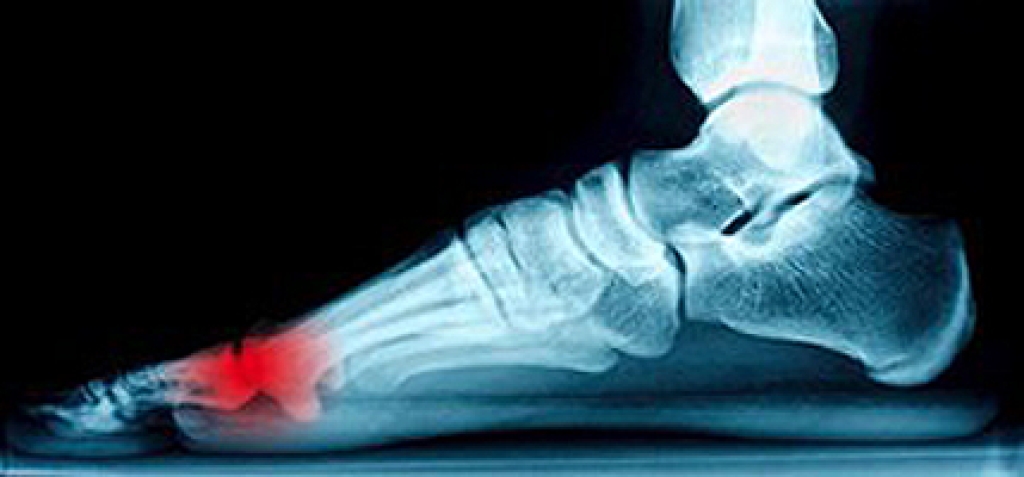

When people age, some common issues that may occur are bone density loss, dry skin, poor circulation, and rough brittle nails. These issues may also affect your foot health if the necessary steps are not taken to alleviate the problems.

It is important to take care of your feet because feet that are injured or diseased can affect your overall health. Having painful feet hinders your ability to do daily activities or may decrease your willingness to do the things that you need to do.